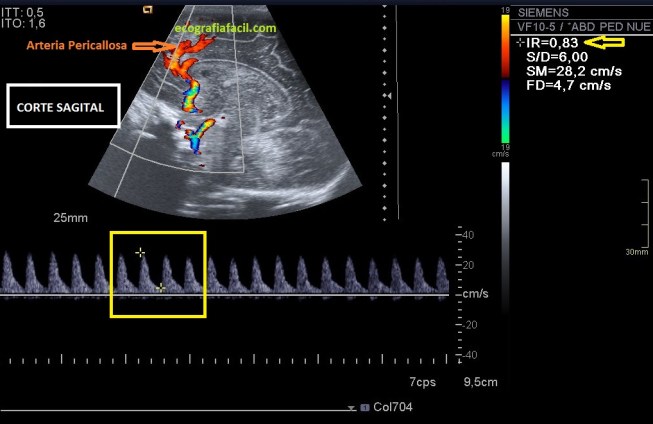

En el estudio con el Doppler del cerebro neonatal y lactante perseguimos la consecución de un valor que nos dará el IR o Índice de Resistencia. En este enlace os dejo un trabajo de la Universidad de Zaragoza donde vais a comprender perfectamente los pormenores de la importancia de este IR, valor que calcularemos mediante el Doppler Pulsado de dos arterias, la Arteria Pericallosa (Corte Sagital) y algunas de las Arterias Cerebrales, te recomiendo estudiarla en corte Coronal. Ambos cortes se realizan a través de la fontanela anterior.

Este registro dará un valor, que según la edad de la/el paciente tendrá unos valores de normalidad en unas tablas. Si este valor está alterado puede deberse a varios motivos de índole patológico, por ejemplo:

–HEMORRAGIA INTRAVENTRICULAR, Valor IR Aumentado.

–HIDROCEFALIA, Valor IR Aumentado.

–ASFIXIA, Valor IR Disminuido.

–DUCTUS: Valor IR alterado por:

Observa la flecha amarilla de las imágenes, en un valor conseguido por la medida en el espectro arterial de cada arteria.

Observe the yellow arrow of the images, in a value obtained by the measurement in the arterial spectrum of each artery.